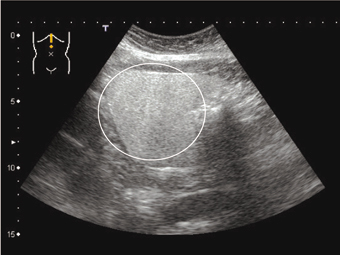

2.肝腎コントラスト

肝臓と右腎を同一画面そして同一深さに表示してエコーレベルの相違を見る「肝腎コントラスト」という評価法である.肝臓への脂肪沈着があきらかにある場合は,そのエコーレベルの差が肝腎コントラスト陽性となり,脂肪肝をみていくうえで重要な所見である(図8.9).

ピットホールは,胆汁うっ滞,うっ血肝,急性肝炎の回復期などで肝実質のエコー輝度が上昇している場合がある.